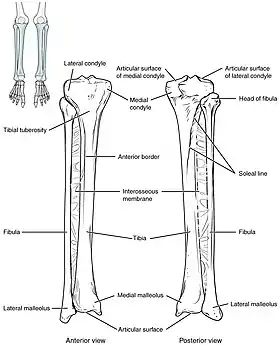

The tibia IO insertion site is just below the medial condyle, labeled in this picture. | |

The needle is injected through the bone's hard cortex and into the soft marrow interior which allows immediate access to the vascular system. The IO needle is positioned at a 90 degree angle to the injection site, and the needle is advanced through manual traction, impact driven force, or power driven.[8] Each IO device has different designated insertion locations. The most common site of insertion is the antero-medial aspect of the upper, proximal tibia as it lies just under the skin and is easily located. This is on the upper and inner portion of the tibia. Other insertion sites include the anterior aspect of the femur, the superior iliac crest, proximal humerus, proximal tibia, distal tibia, sternum (manubrium).[9]